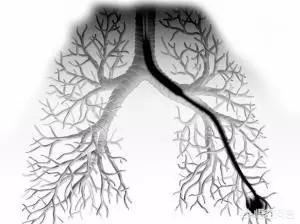

Tout d'abord, l'émergence du terme médical de nodules pulmonaires s'accompagne du développement de l'imagerie médicale et l'émergence de ce que l'on appelle l'imagerie médicale va de pair avec le développement de la science et de la technologie et l'invention d'équipements médicaux, et l'utilisation de ces équipements d'inspection à travers l'examen du corps humain, et permet finalement à nos yeux de voir la structure interne de notre corps, comme "l'ombre" ou "le semblable", afin de faciliter la communication, ces "ombres" ou "semblables" sont imprimées, ce qui est communément appelé "l'ombre" ou "le semblable". "Pour faciliter la communication, l'"ombre" ou le "semblable" sont imprimés, c'est-à-dire que les gens ordinaires sont communément appelés le "film", pour faciliter la communication, l'"ombre" ou le "semblable" sont imprimés, c'est-à-dire que les gens ordinaires sont communément appelés le "film". "film".

En fait, ces films sont les supports de ces images, qui sont pratiques à transporter, et facilitent également la communication entre le médecin et le médecin pendant la visite, ainsi que la communication entre le médecin et le médecin pendant la consultation. Il y a d'abord eu le film radiographique, puis, avec le développement de la technologie médicale, la tomodensitométrie, l'échographie, l'endoscopie, la résonance magnétique nucléaire, le PET-CT et d'autres équipements d'examen, qui sont également apparus dans une variété d'images d'examen. Les différents équipements d'imagerie ont leurs propres avantages et inconvénients. Pour les poumons, la structure interne fine des poumons est clairement représentée par la tomodensitométrie, l'équipement de tomodensitométrie est également amélioré par les progrès de la science sociale et de la technologie, 64 rangées, 128 rangées, 256 rangées sont apparues, plus la technologie est avancée, plus le temps de balayage est court, plus la plage de balayage est large, plus l'épaisseur est fine, plus la quantité d'informations obtenues est importante pour vérifier les lésions subtiles, mais aussi plus la technologie est avancée, plus le temps de balayage est court, plus la plage de balayage est large, plus l'épaisseur est fine, plus les informations sont importantes pour vérifier les lésions subtiles. Plus la technologie est avancée, plus la durée du balayage est courte, plus la plage de balayage est grande, plus l'épaisseur du balayage est fine, plus les informations obtenues sont nombreuses, plus les lésions subtiles peuvent être détectées. Par conséquent, il existe de nombreuses lésions subtiles qui ne peuvent pas être détectées par les rayons X, mais qui peuvent l'être par la tomodensitométrie.

L'image du thorax permet non seulement de trouver des nodules pulmonaires, mais aussi de montrer clairement l'emplacement, la taille, la forme et les caractéristiques des nodules, ce qui suggère que les nodules pulmonaires sont situés dans les poumons et qu'ils se sont accumulés et formés, ce qui correspond à la dénomination médicale chinoise de "stagnation pulmonaire", "stagnation" et "noyaux de flegme", fournissant ainsi une base pour l'identification de la maladie en médecine traditionnelle chinoise. Elle est conforme à la médecine chinoise "stagnation pulmonaire", "accumulation" et "noyaux de flegme", et fournit une base pour l'identification des nodules pulmonaires en médecine chinoise.